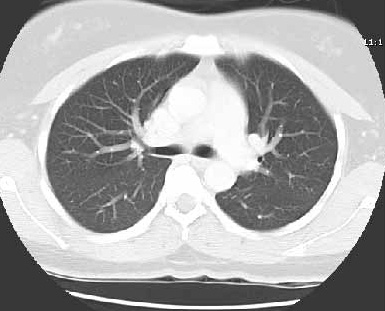

Image tomodensitographie computerisation ( CT scan , fenetre parenchymateuse ) :Un coupe horizontal du thorax a travers D6 . Le mediastin , aort ascendent, veinecave sup, le troc de artere pulmonaire , peut detecte et se voyaient net en image . La region sous carenaire et image clair de la bronche souche droite et gauche se voyaient  aussi  ...